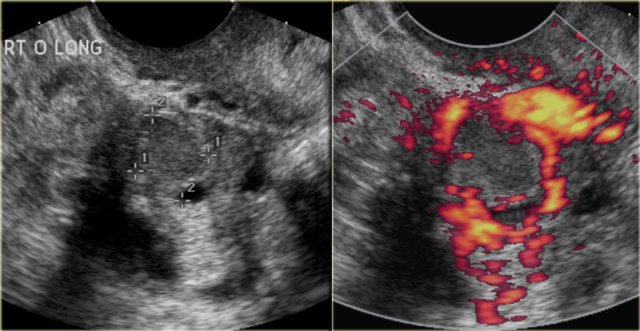

The transvaginal ultrasound images show a small complex ovarian cyst with wall vascularity on power Doppler analysis.

The characteristic circular Doppler appearance is called the 'ring of fire'.

Note, there is good through-transmission and no internal vascularity, consistent with a, partially involuted, corpus luteum cyst.

Another case with the typical the 'ring of fire' on ultrasound.